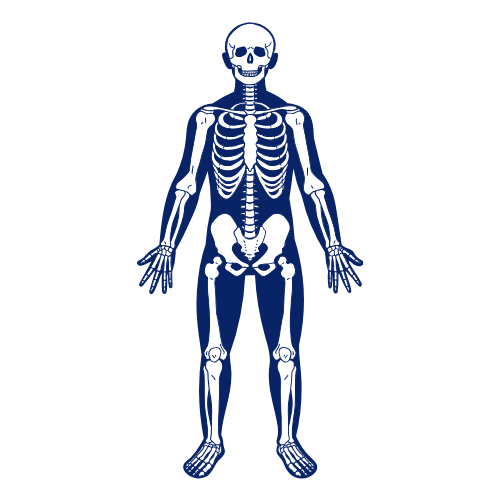

Es un procedimiento no invasivo e indoloro que ofrece una visión detallada de diversas áreas del cuerpo, permitiendo diagnósticos precisos y personalizados.

Resonancia magnética músculo esquelético